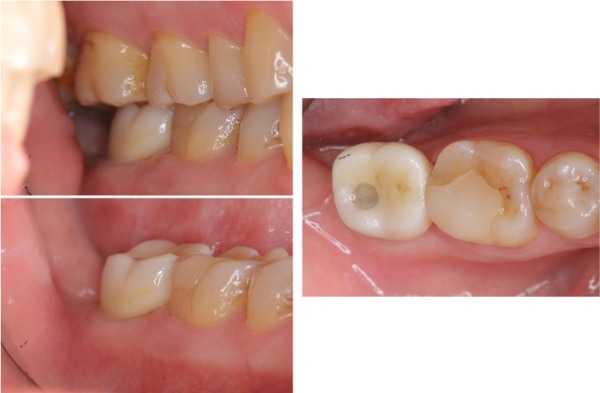

治療前,二次蛀牙,咬頭受損

蛀牙未到牙髓